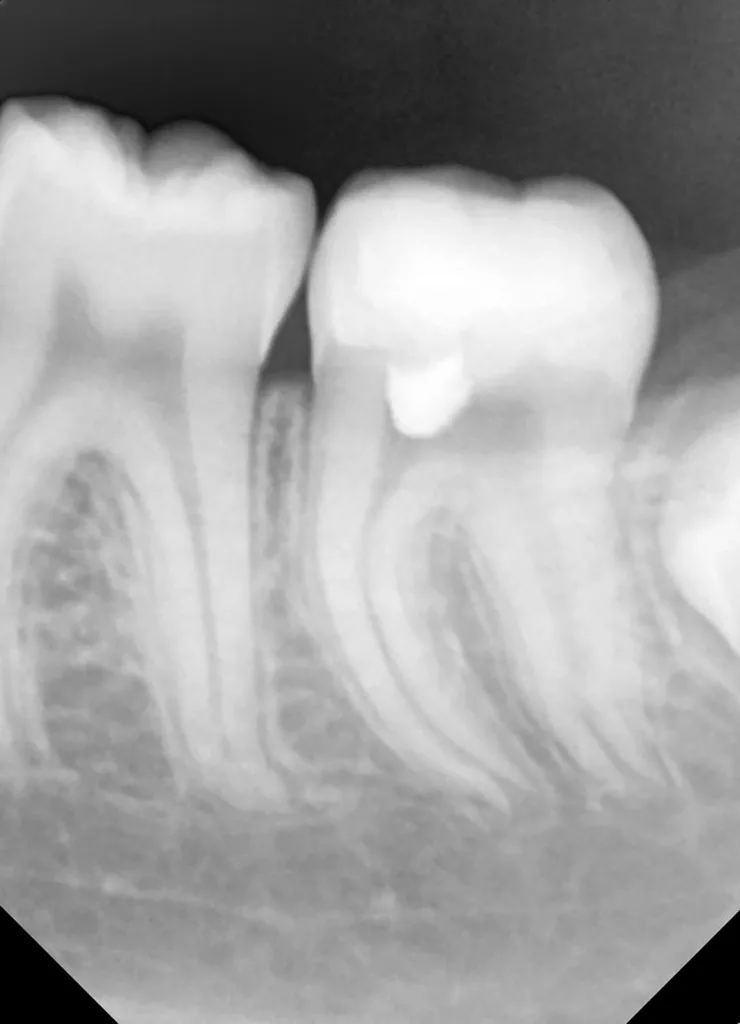

Bei routinemäßigen Röntgenkontrollen ergeben sich manchmal Zufallsbefunde unklarer Genese. So stellt sich beispielsweise bei der Betrachtung der Abbildung 1 die Frage, wie sich ein Zahnhartsubstanzdefekt so schnell entwickeln konnte. Ein weiteres Röntgenbild (Abb. 2), das vor dem Zahndurchbruch aufgenommen wurde, zeigt jedoch, dass es sich in diesem Fall nicht um Karies, sondern um die sogenannte präeruptive intrakoronale Resorption (PEIR) handelt. Für diesen Befund finden sich in der Fachliteratur auch noch andere Bezeichnungen wie „idiopathic external resorption of unerupted permanent teeth“ [1], „intra-follicular caries“ [2], „radiolucent lesions resembling caries“ [3], „occult caries“ [ 4] oder „pre-eruptive caries“ [5].

V. Slabkovskyi, O. LiutikovJahr vor dem Durchbruch des Zahnes 36.

Das fünfjährige Mädchen stellte sich 2017 zur jährlichen Routinekontrolle vor. Im Rahmen der Untersuchung wurden Röntgenaufnahmen der Milchmolaren gemacht (Abb. 2). Der klinische und radiologische Befund der vor uns früher gelegten Kompositfüllungen war gut, es wurde allerdings eine PEIR an den noch nicht durchgebrochenen ersten bleibenden Molaren festgestellt (Abb. 2). Den Eltern wurde empfohlen, sich unverzüglich bei Beginn des Durchbruchs der ersten Molaren erneut zur Behandlung vorzustellen. Ein Jahr später erschien die junge Patientin schmerzfrei zur Kontrolle. Der Zahn 36 war noch teilweise mit Gingiva bedeckt. Auf einer neuen Röntgenaufnahme (Abb. 1) wurde die PEIR-Läsion mit unveränderter Größe in pulpanahen Bereichen bestätigt (Grad 3 der Läsion nach Seow). Der Zahnschmelz sah intakt aus, es konnte kein pathologischer periapikaler Befund bei den noch nicht ausgewachsenen Zahnwurzeln festgestellt werden. Daraufhin wurden die verschiedenen Behandlungsmöglichkeiten von Fissurenversiegelung bis Vitalerhaltung der Zahnpulpa mit den Eltern des Kindes besprochen.